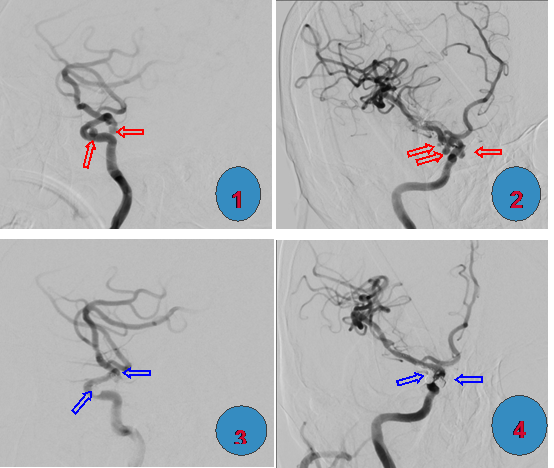

图1、图2:颈内动脉多发(3个)动脉瘤(图中红箭所示);

图3、图4: 行颅内动脉瘤弹簧圈栓塞术+支架植入术后复查正侧位造影示动脉瘤消失,颅内血管血流通畅(图中蓝箭所示)。